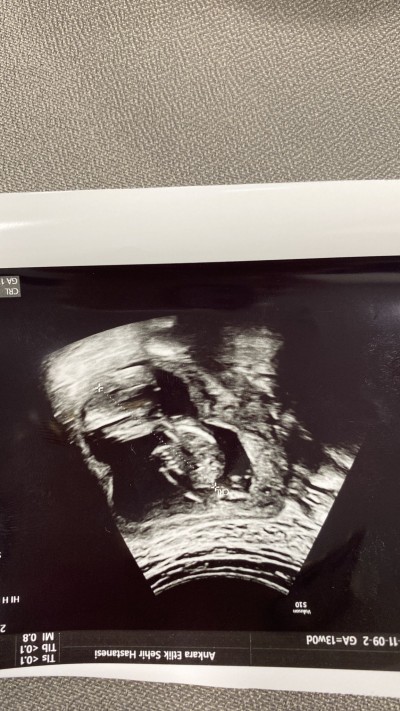

Anlayabilen var mı 13 haftalıkken doktor erkeğe benziyor dedi. Ama net söylemedi sizce ne olabilir?

Bacak arasında çıkıntı var erkek sanırım :)

Gözüküyor ya arada kısa minnak bişey

Doğru erkekmiş :)